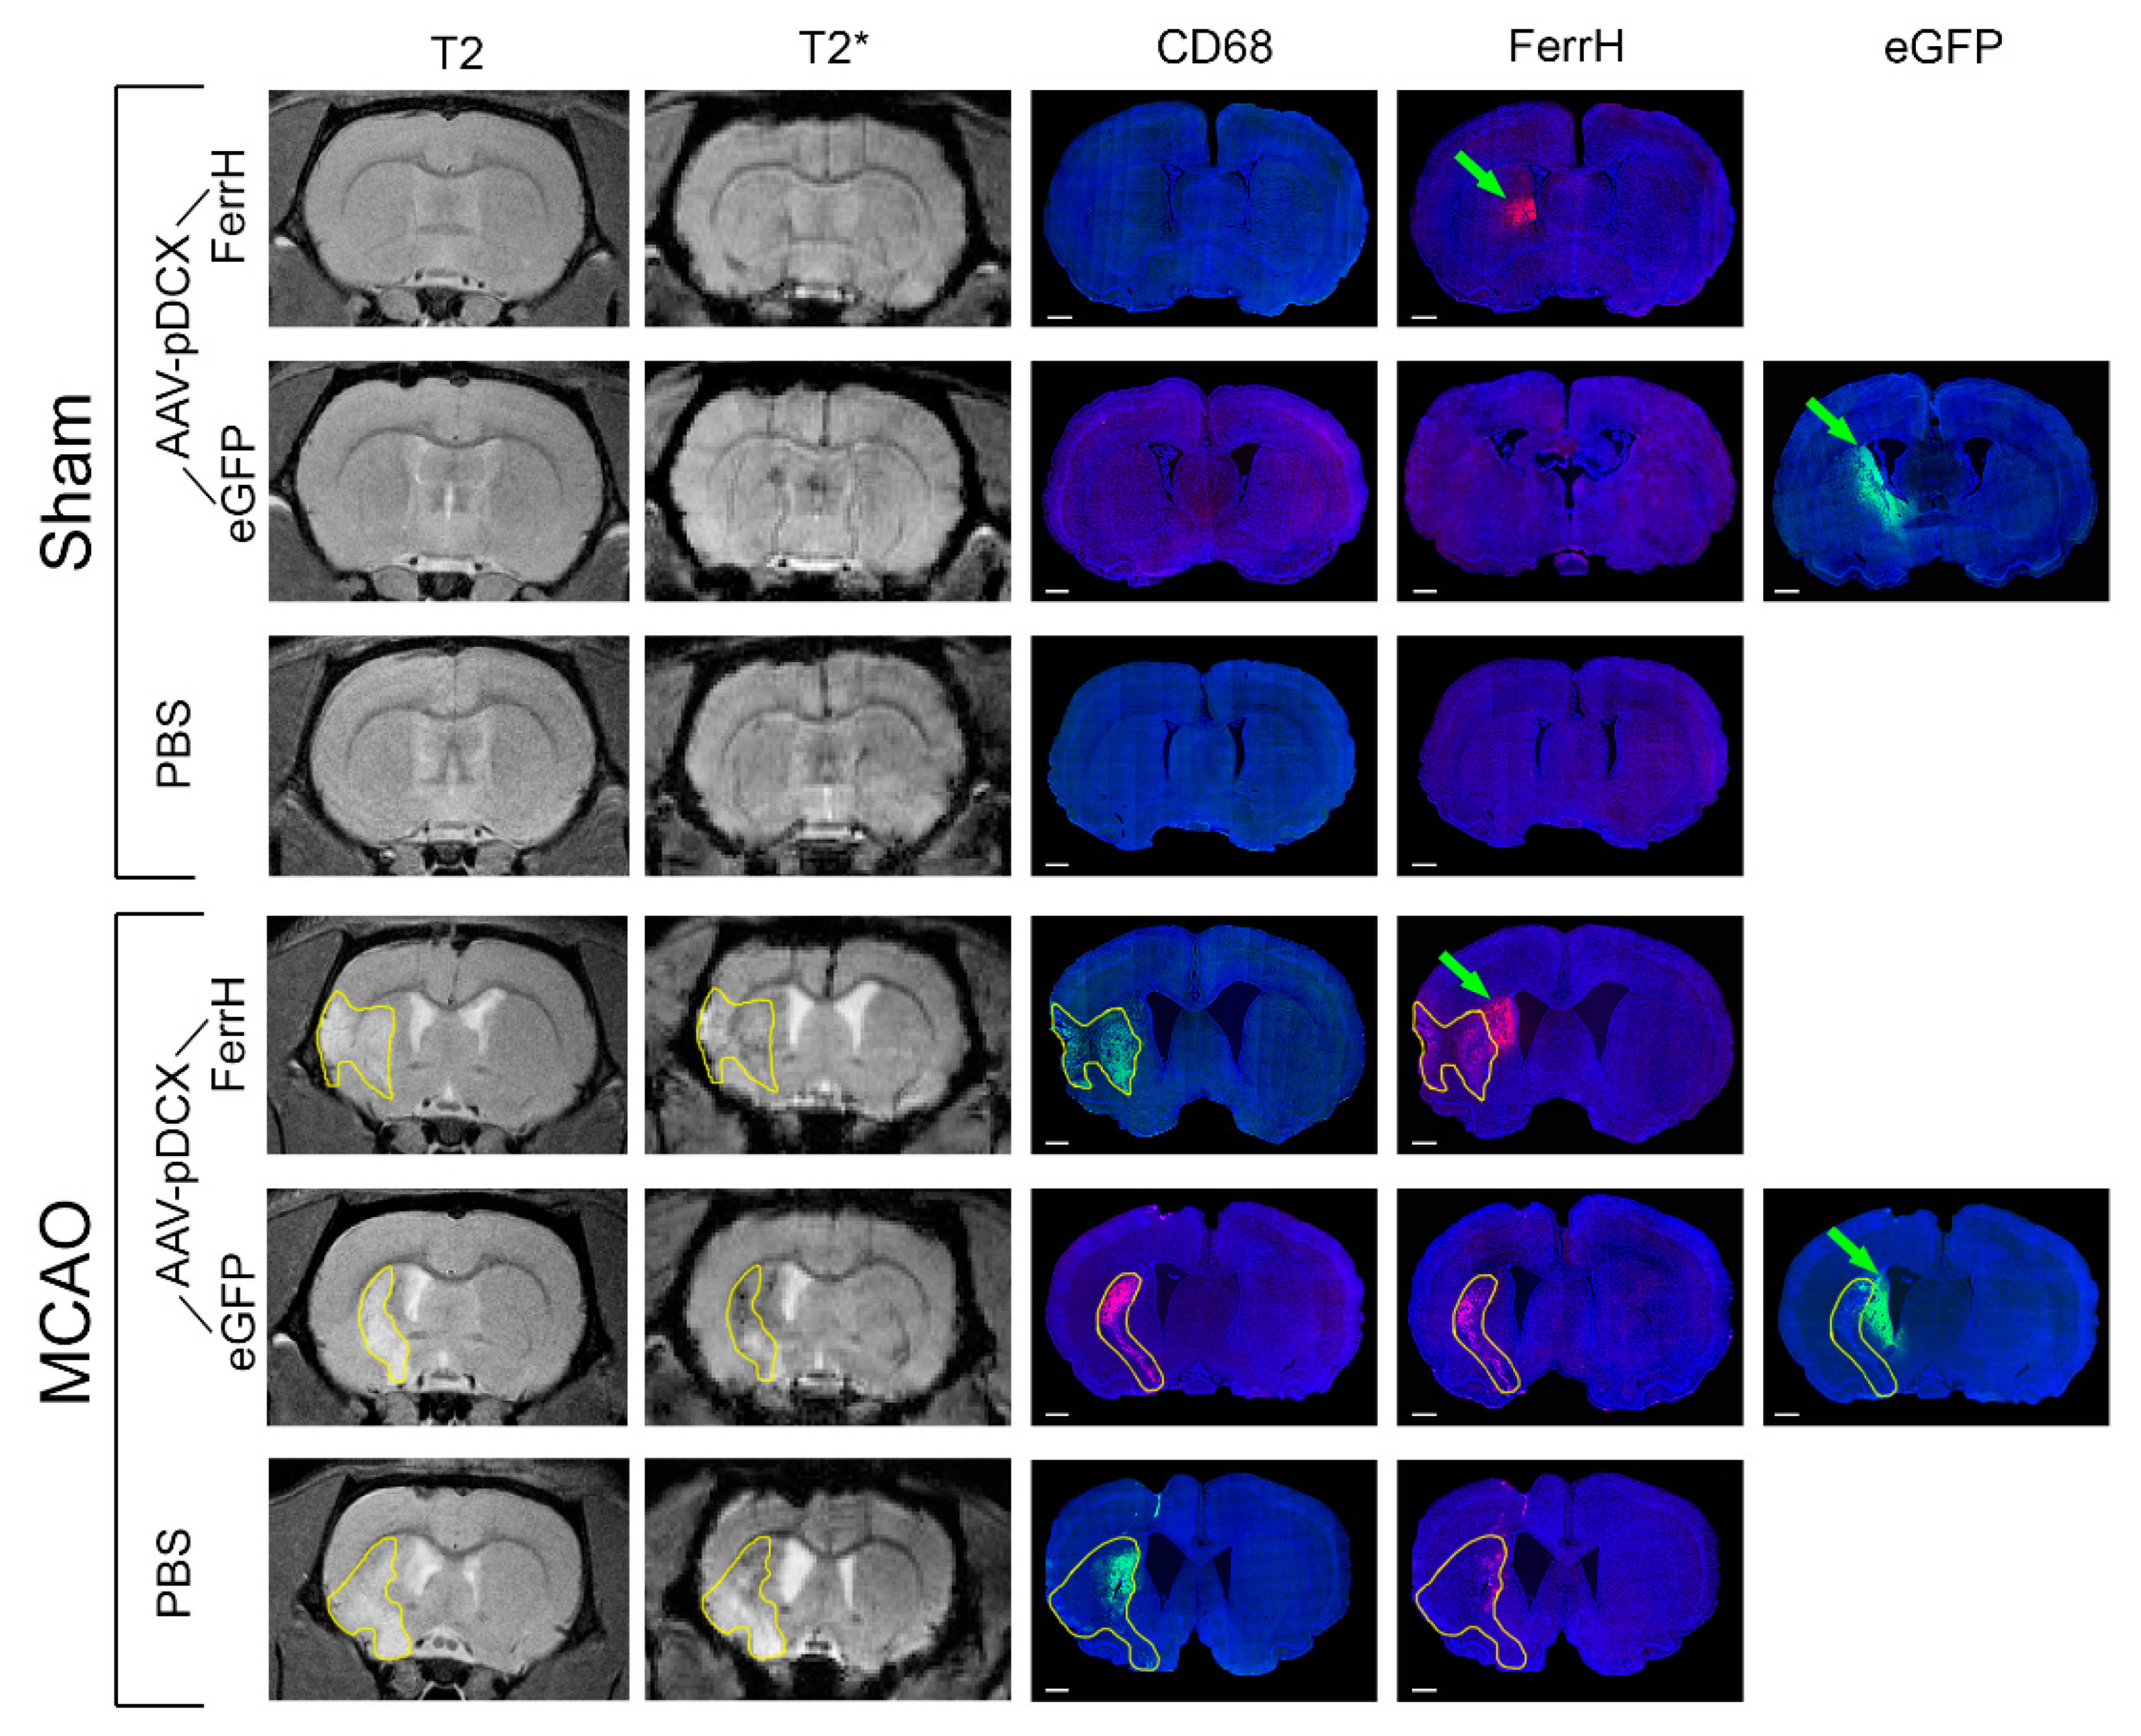

2.3. T2* Signal Hypointensity Correlates with FerrH and eGFP Accumulation

- Results of our study showed that rat brain could be successfully infected with AAV-pDCX-FerrH and AAV-pDCX-eGFP viral vectors for expression of either ferritin or eGFP. Both vectors caused at about 20% decrease in signal hypointensity in the areas near the SVZ on T2*-weighted MRI at one month after intracranial injection of the viral constructs.

- The location of the signal hypointensity areas coincides with zones of ferritin and eGFP accumulation in immunohistochemical slides and zones of iron accumulation in Prussian blue staining a month after viral injection. RT-PCR data confirmed upregulated expression of the ferritin in the corpus callosum and caudoputamen in the left hemisphere of the rat brain on day 7 after intracerebral injected of the adenoviral vector construct.